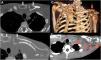

(A‒B) CT images obtained in the axial plane and bone window showing lytic lesion signs with cortical destruction of the left clavicle and manubrium and no periosteal reaction (white arrows). (C) Volume-rendered 3D image also demonstrating multiple osteolytic lesions with cortical rupture of the manubrium, sternum, and left clavicle (red arrows). (D) CT image obtained in the axial plane and soft-tissue window depicting fluid collection around the bony destruction of the left clavicle (red arrowheads).

An 18-year-old man came to the emergency room due to fever, productive cough, asthenia, 30 kg weight loss, generalized lymphadenopathy, and migratory polyarthritis in the last 6-months. Laboratory test findings were unremarkable. A blood test for human immunodeficiency virus was negative. Computed Tomography (CT) showed multiple well-delimited osteolytic lesions with no sclerotic halo or contrast enhancement affecting the sternum, elbows, ilium, sacroiliac joint, knees, and ankles, with no evidence of periosteal reaction (Fig. 1). There was no sign of pulmonary involvement. Metastatic disease was suspected. On Positron Emission Tomography (PET)/CT, Fluorodeoxyglucose (FDG) uptake was intense in the osteolytic lesions (maximum standard uptake = 14.3; Fig. 2) and some mediastinal lymph nodes. The diagnosis of Paracoccidioidomycosis (PCM) was confirmed through direct mycological examination of a lymph-node biopsy sample, which demonstrated spherical, thick-walled yeast cells of variable size, with peripheral buds protruding from a central cell, a pattern called the “pilot's wheel”, characteristic of Paracoccidioides brasiliensis. Paracoccidioides spp. also grew in the culture after 4-weeks. The patient was treated with antifungal drugs and the lesions improved.